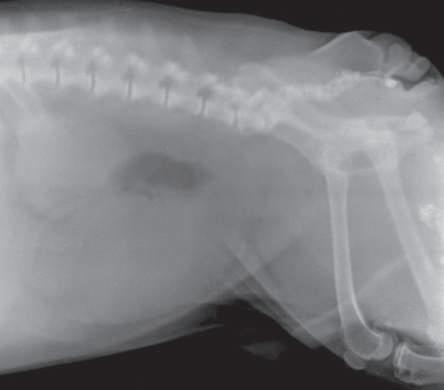

Imagen radiográfica en proyección lateral izquierda derecha, en la cual se aprecia vejiga plétora, con cambios de densidad en la luz vesical correspondientes a zonas aparentemente nodulares que corresponden a irregularidades en el contenido vesical como la presencia de urolitos (p. 81).